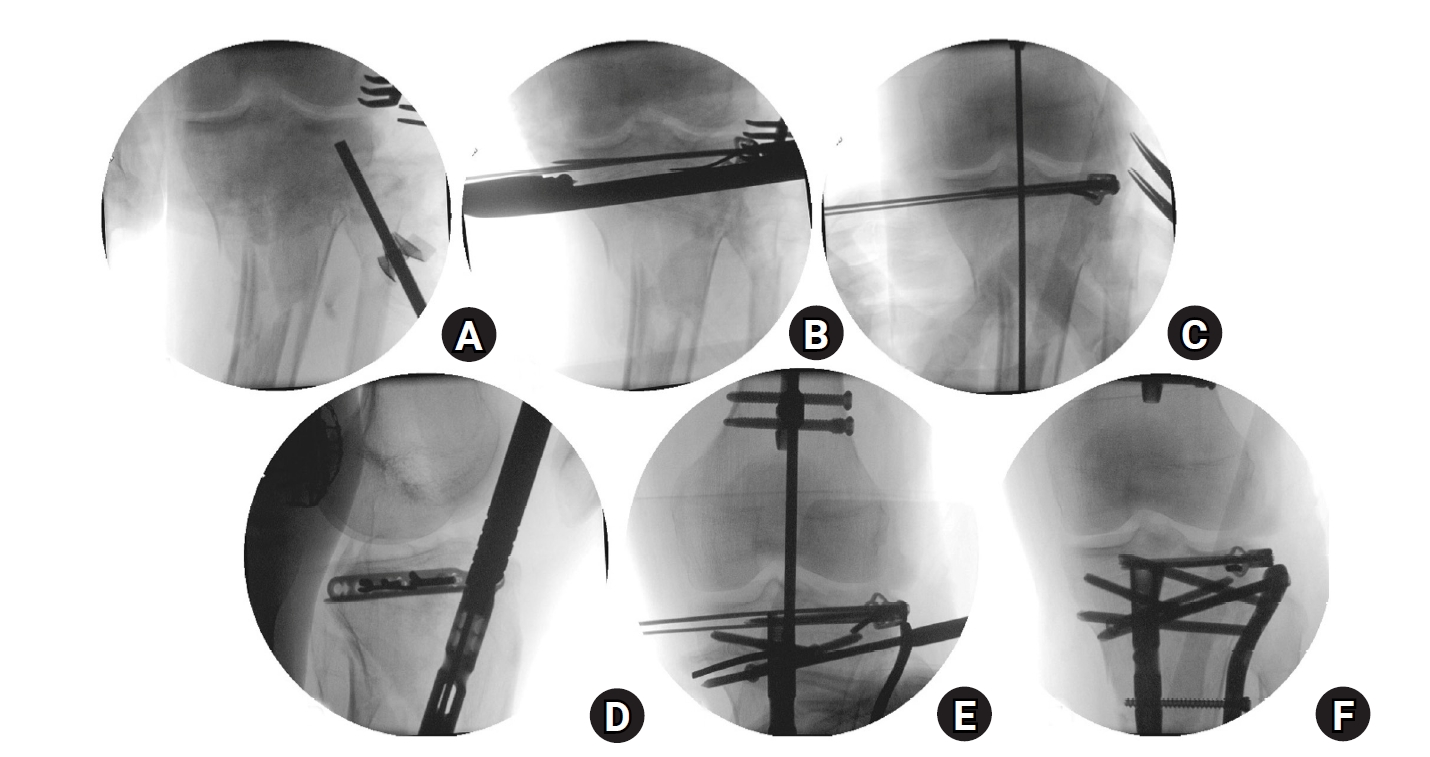

Fig. 6.

Fluoroscopic images and schematic illustrations of the rim plate-assisted intramedullary nail and plate combination technique. (A) Lateral plateau depression was elevated. (B, C) A contoured 2.7-mm variable-angle locking compression plate was applied with medial-to-lateral compression and fixed to unify the plateau into a single segment. (D) Intramedullary nailing was performed via the suprapatellar approach. (E) Alignment was confirmed with a rod. (F) A 4.5-mm proximal lateral tibia plate was added for final fixation.

Fig. 6. Fluoroscopic images and schematic illustrations of the rim plate-assisted intramedullary nail and plate combination technique. (A) Lateral plateau depression was elevated. (B, C) A contoured 2.7-mm variable-angle locking compression plate was applied with medial-to-lateral compression and fixed to unify the plateau into a single segment. (D) Intramedullary nailing was performed via the suprapatellar approach. (E) Alignment was confirmed with a rod. (F) A 4.5-mm proximal lateral tibia plate was added for final fixation.

As in case 1, the procedure started with converting the tibial plateau fracture into a single segment using a rim plate. An anterolateral approach was chosen because of the anterolateral location of the main fracture. The patient had a lateral condylar depression of the tibial plateau, which was initially elevated using an impactor (Fig. 6A). After the elevation of the depressed fragment, Kirschner wires were temporarily fixed through the inside-out technique [9]. A 2.7-mm VA-LCP was then shaped and positioned, followed by medial-to-lateral compression using a colinear clamp (Fig. 6B). Both cortical and locking screws were inserted through the VA-LCP, which connected the plateau fragments into a single segment (Fig. 6C). A suprapatellar approach was employed for IM nailing (Fig. 6D). As in case 1, only three cancellous screws could be inserted into the proximal fragment through the IM nail. To enable immediate full weight bearing, an additional plate was applied to augment fixation, which completed the NPC technique (Fig. 6F). In this patient, the longest available 4.5-mm LCP proximal tibia plate did not provide sufficient construct length. Therefore, a 4.5-mm LCP proximal lateral tibia plate was used instead; this plate has a proximally oblique design, in contrast to the sharply angled, inverted “L”-shaped design of the standard proximal tibia plate. Postoperative plain radiographs and CT images are shown in Fig. 7.